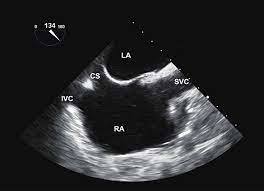

you can see the crsital terminalis between SVC and RAA

A

Mid esophageal Bicaval view

90 - 110 degree